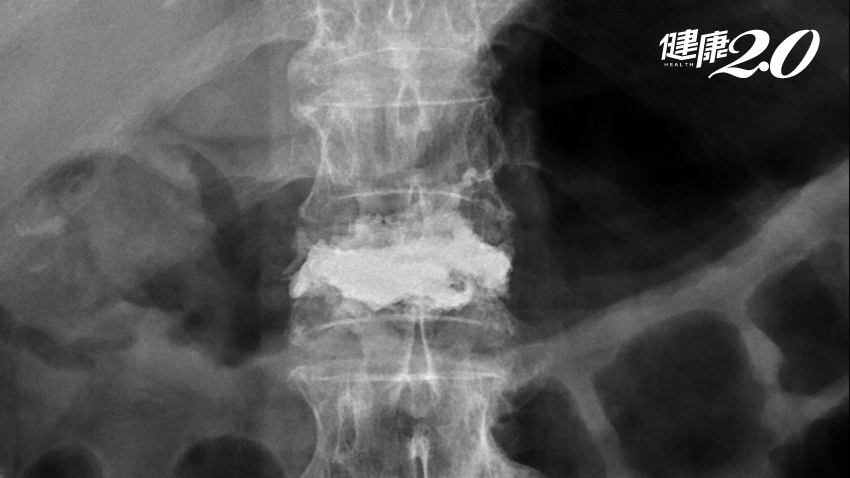

▲ 術後陳阿嬤脊椎X光攝影(左圖);手術傷口小,約只有一個針頭大小(右圖)。